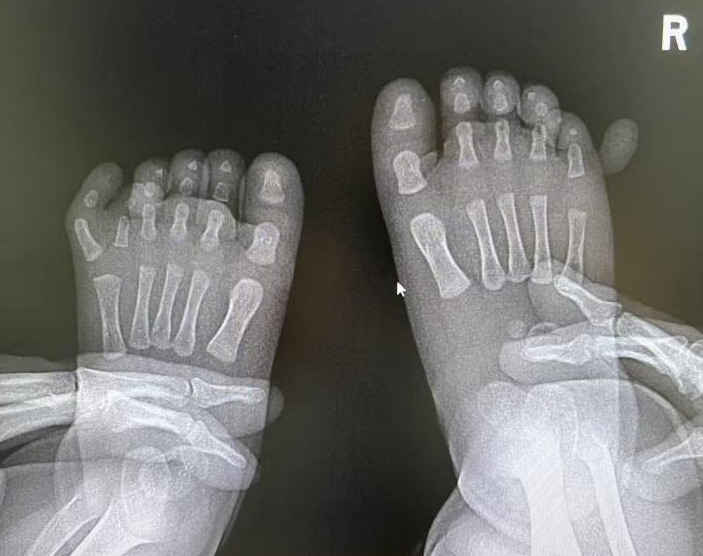

术后复查 X线:

在团队的精心呵护下,小宝宝平稳度过了围手术期。术后两周复查,伤口愈合良好,顺利拆线。

令人欣喜的是,宝宝的手指和足趾活动自如,抓握、蹬踏均不受影响。手足外形恢复理想,几乎看不出手术的痕迹。这个结果,让一直悬着心的家长终于舒展了眉头,露出了安心的笑容。这次成功的手术,为宝宝的未来清除了身体上的障碍,也卸下了全家心理上的负担。